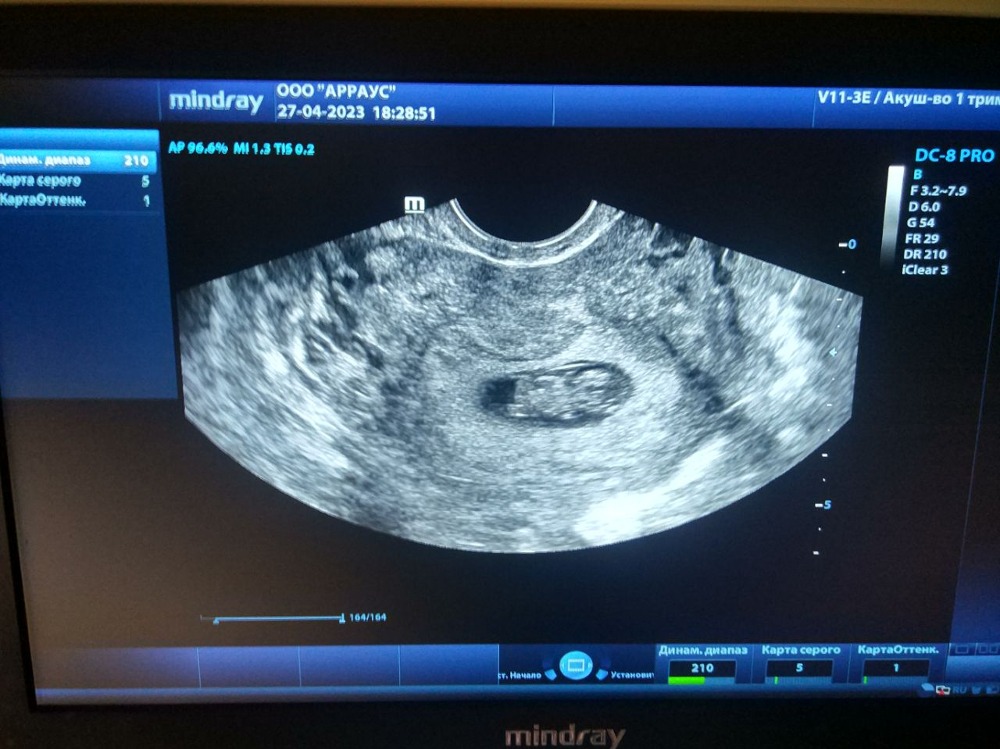

Дарья , вот наше узи на сроке 8 недель +. Дочка тут уже нам рукой махала))) узист так и сказала: смотрите, доропыга вам привет передает))) так что, хгч уже такая ерунда. Изображение